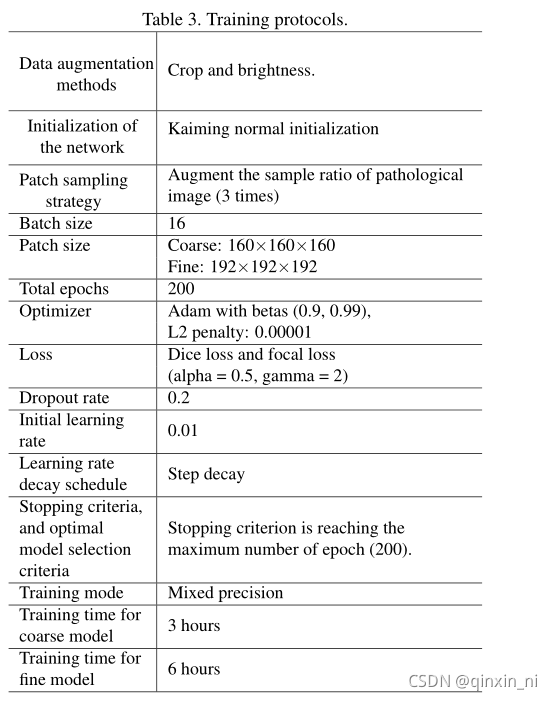

Pipeline

分割算法流程如下图:

粗分割输入大小为160, 160, 160, 细分割为192, 192, 192。由于粗分割用于器官定位,采用更低的输入分辨率、复杂度更低的网络结构;根据粗分割mask,裁剪腹部区域图像块作为细分割的输入,这样能够降低不同case图像块之间的差异。

本文在GPU中实现resampe和normalization,来加快推理速度。由于后处理比较耗时,本文采用异步实现细分割后处理。本文采用C++ library实现保留最大连通区域 cc3dhttps://github.com/seung-lab/connected-components-3d/tree/424328a11d712b38a032b57d8b25fe2d09051787 https://github.com/seung-lab/connected-components-3d/tree/424328a11d712b38a032b57d8b25fe2d09051787以及提取目标特征fastremap